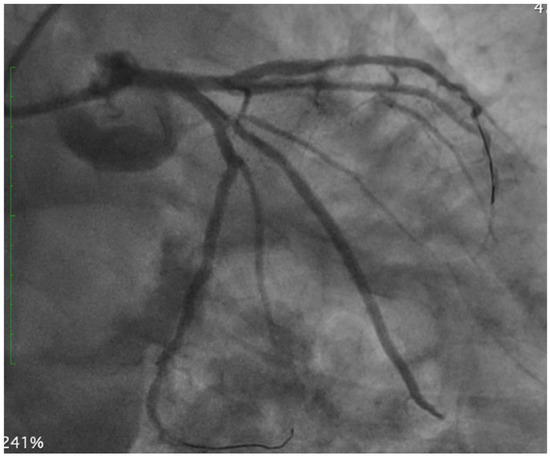

Non-invasive coronary evaluation with CCTA enables the comprehensive qualitative and quantitative analysis of atherosclerotic plaque features, lumen dimensions, and lesion length. These parameters translate directly into improved PCI planning and procedural outcomes. Plaques with a high calcium burden may lead to suboptimal stent expansion and apposition with an increased rate of target vessel failure, while incomplete plaque coverage or inaccurate lesion length estimation—often related to limited fluoroscopic projection—can result in inappropriate stent sizing and higher risk of target-vessel revascularization [2,3]. As shown in Figure 1, pre-procedural CCTA revealed a heavily calcified proximal–mid LAD lesion, with semi-circumferential to near-concentric calcium distribution on MPR cross-sections, indicative of a high calcific burden and ultimately requiring orbital atherectomy for adequate plaque debulking.

Figure 1.

Pre-procedural CCTA assessment of a heavily calcified proximal−mid LAD lesion. Multiplanar reconstruction (MPR) and cross-sectional imaging demonstrate semi-circumferential to near-concentric calcium, consistent with a high calcific burden and supporting the need for orbital atherectomy during PCI to achieve effective lesion preparation. LAD: left anterior descending.